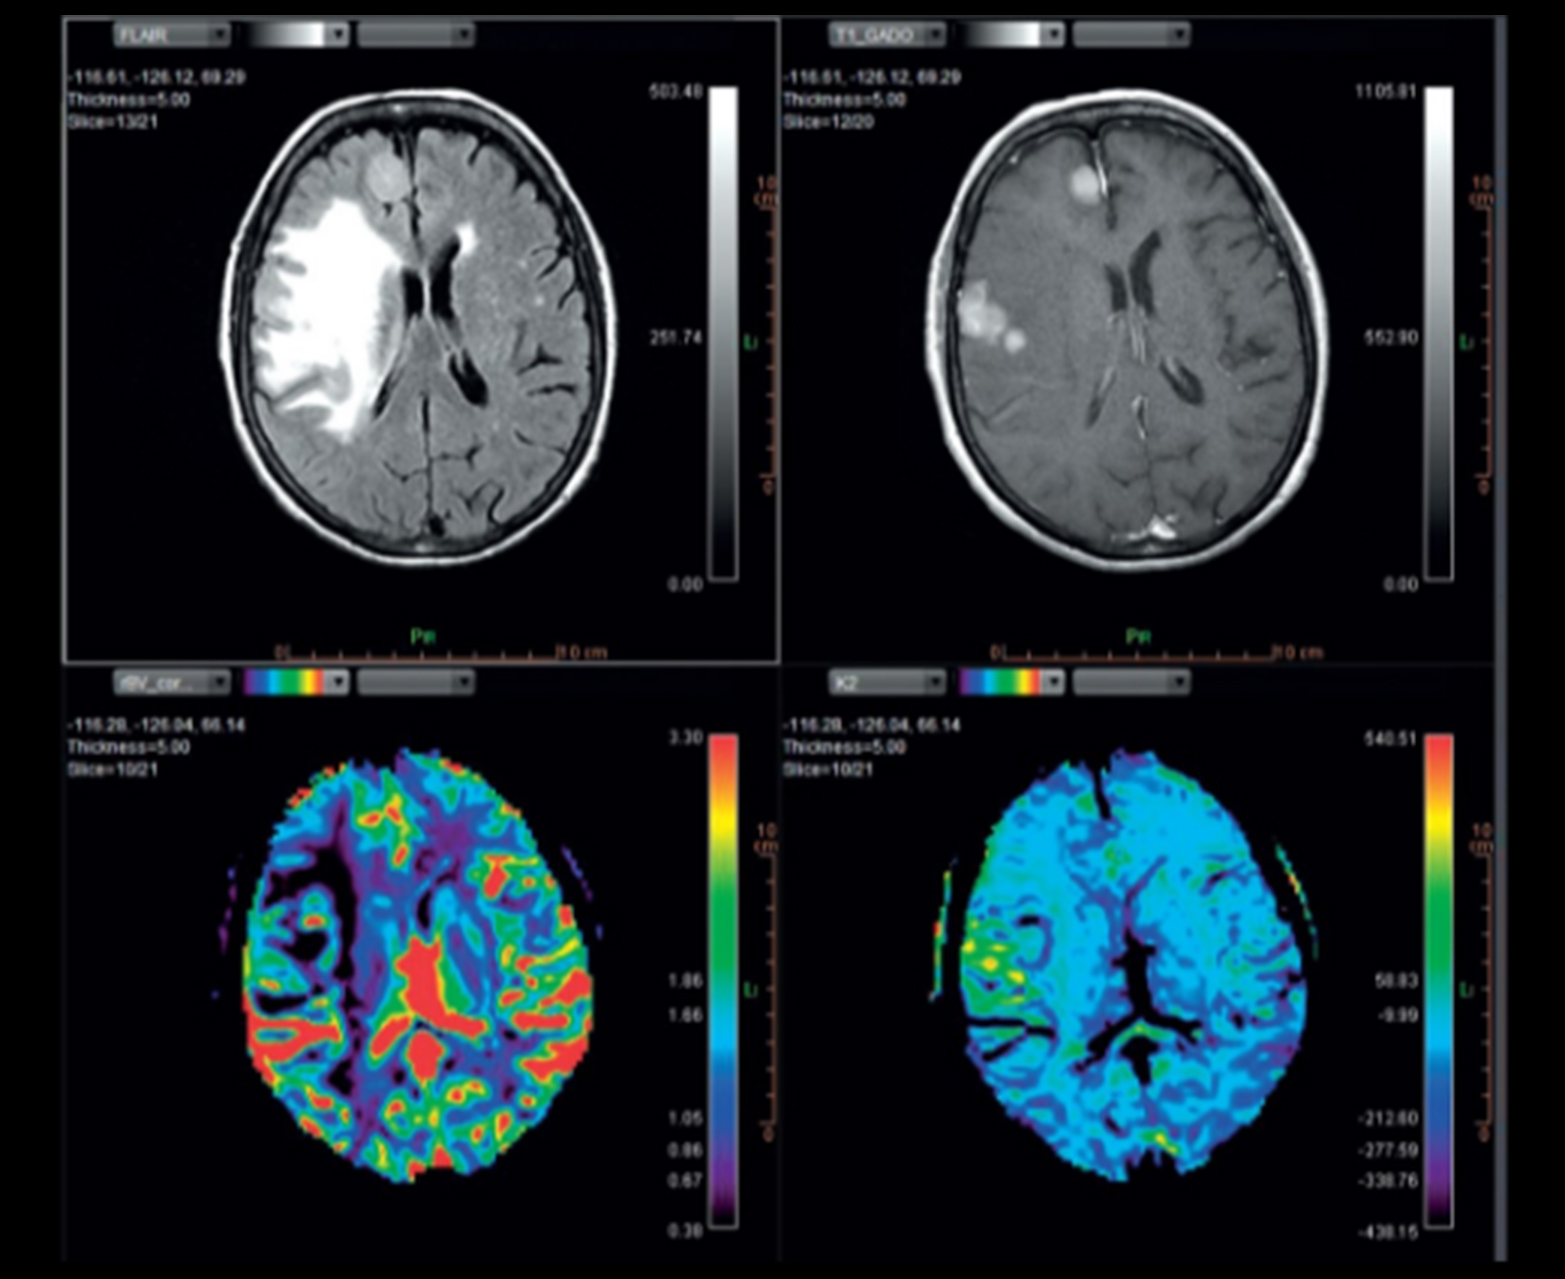

Многопараметрическое настраиваемое отображение карт диффузии и перфузии, включая карты rCBV_corrected и K2

Отслеживание волокна и объединение с обычными картами

Мгновенный и стандартизированный отчет об инсульте с автоматическим вычислением несоответствия